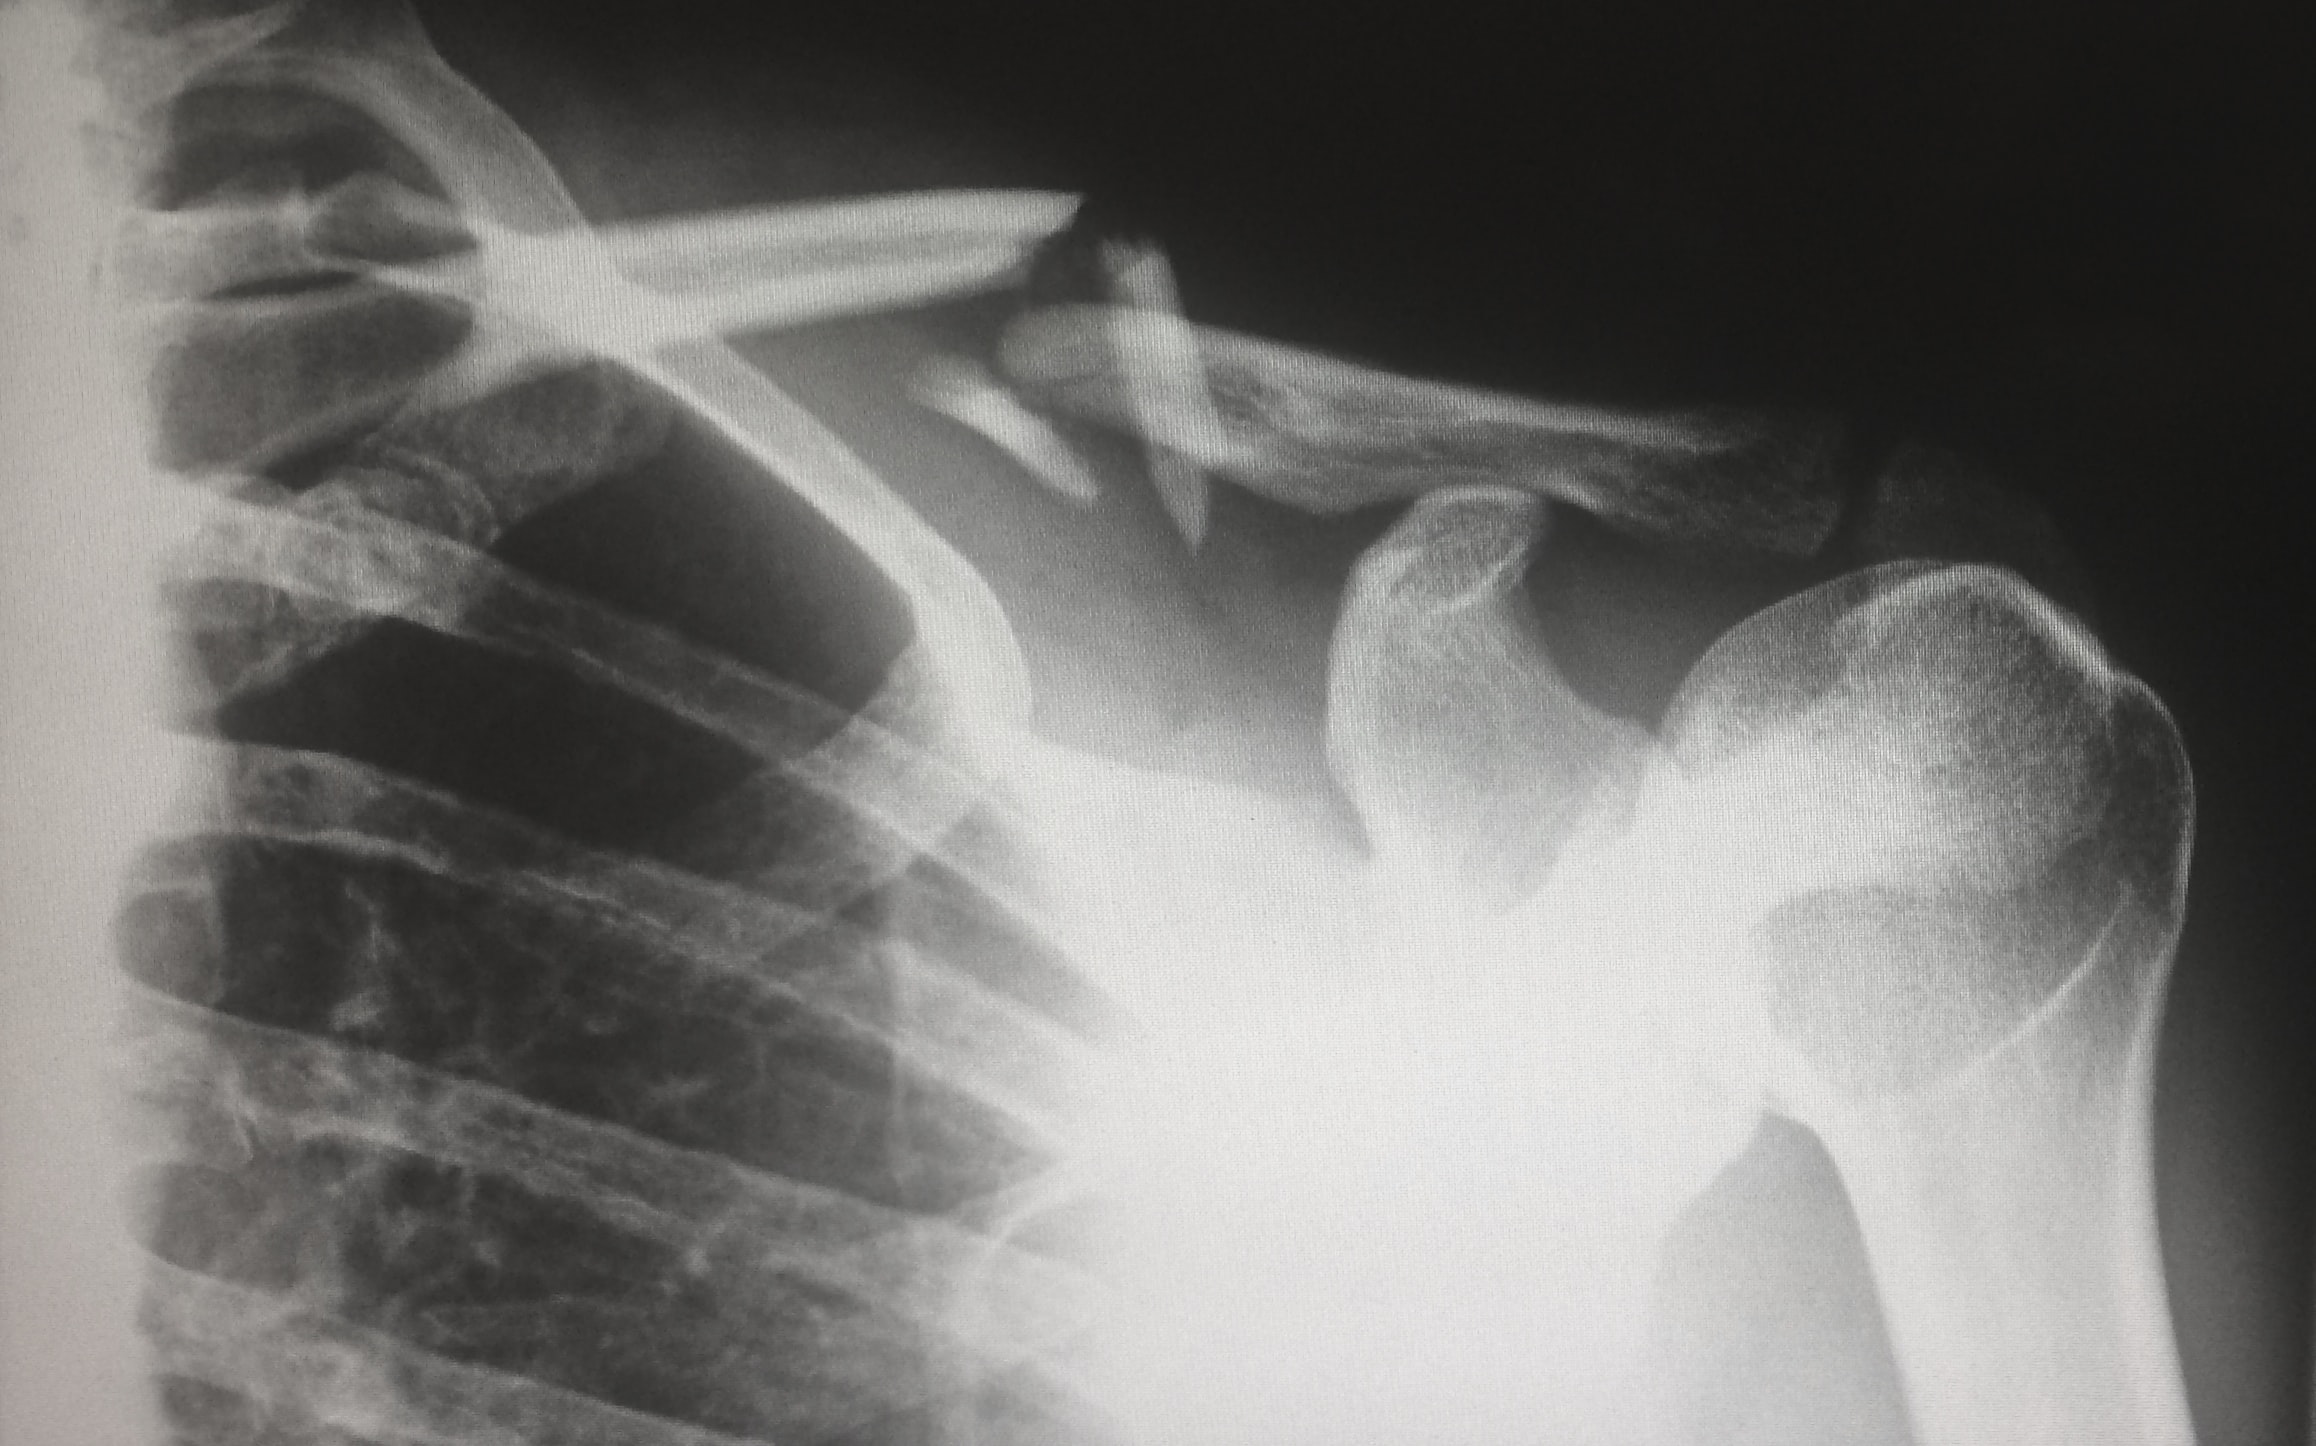

The MLHD has promised two bone surgeons for Griffith Base Hospital. (Unsplash: Harlie Raethel)

Griffith residents have had to travel to Wagga Wagga to receive orthopaedic treatment. (ABC Riverina: Michael Patterson)